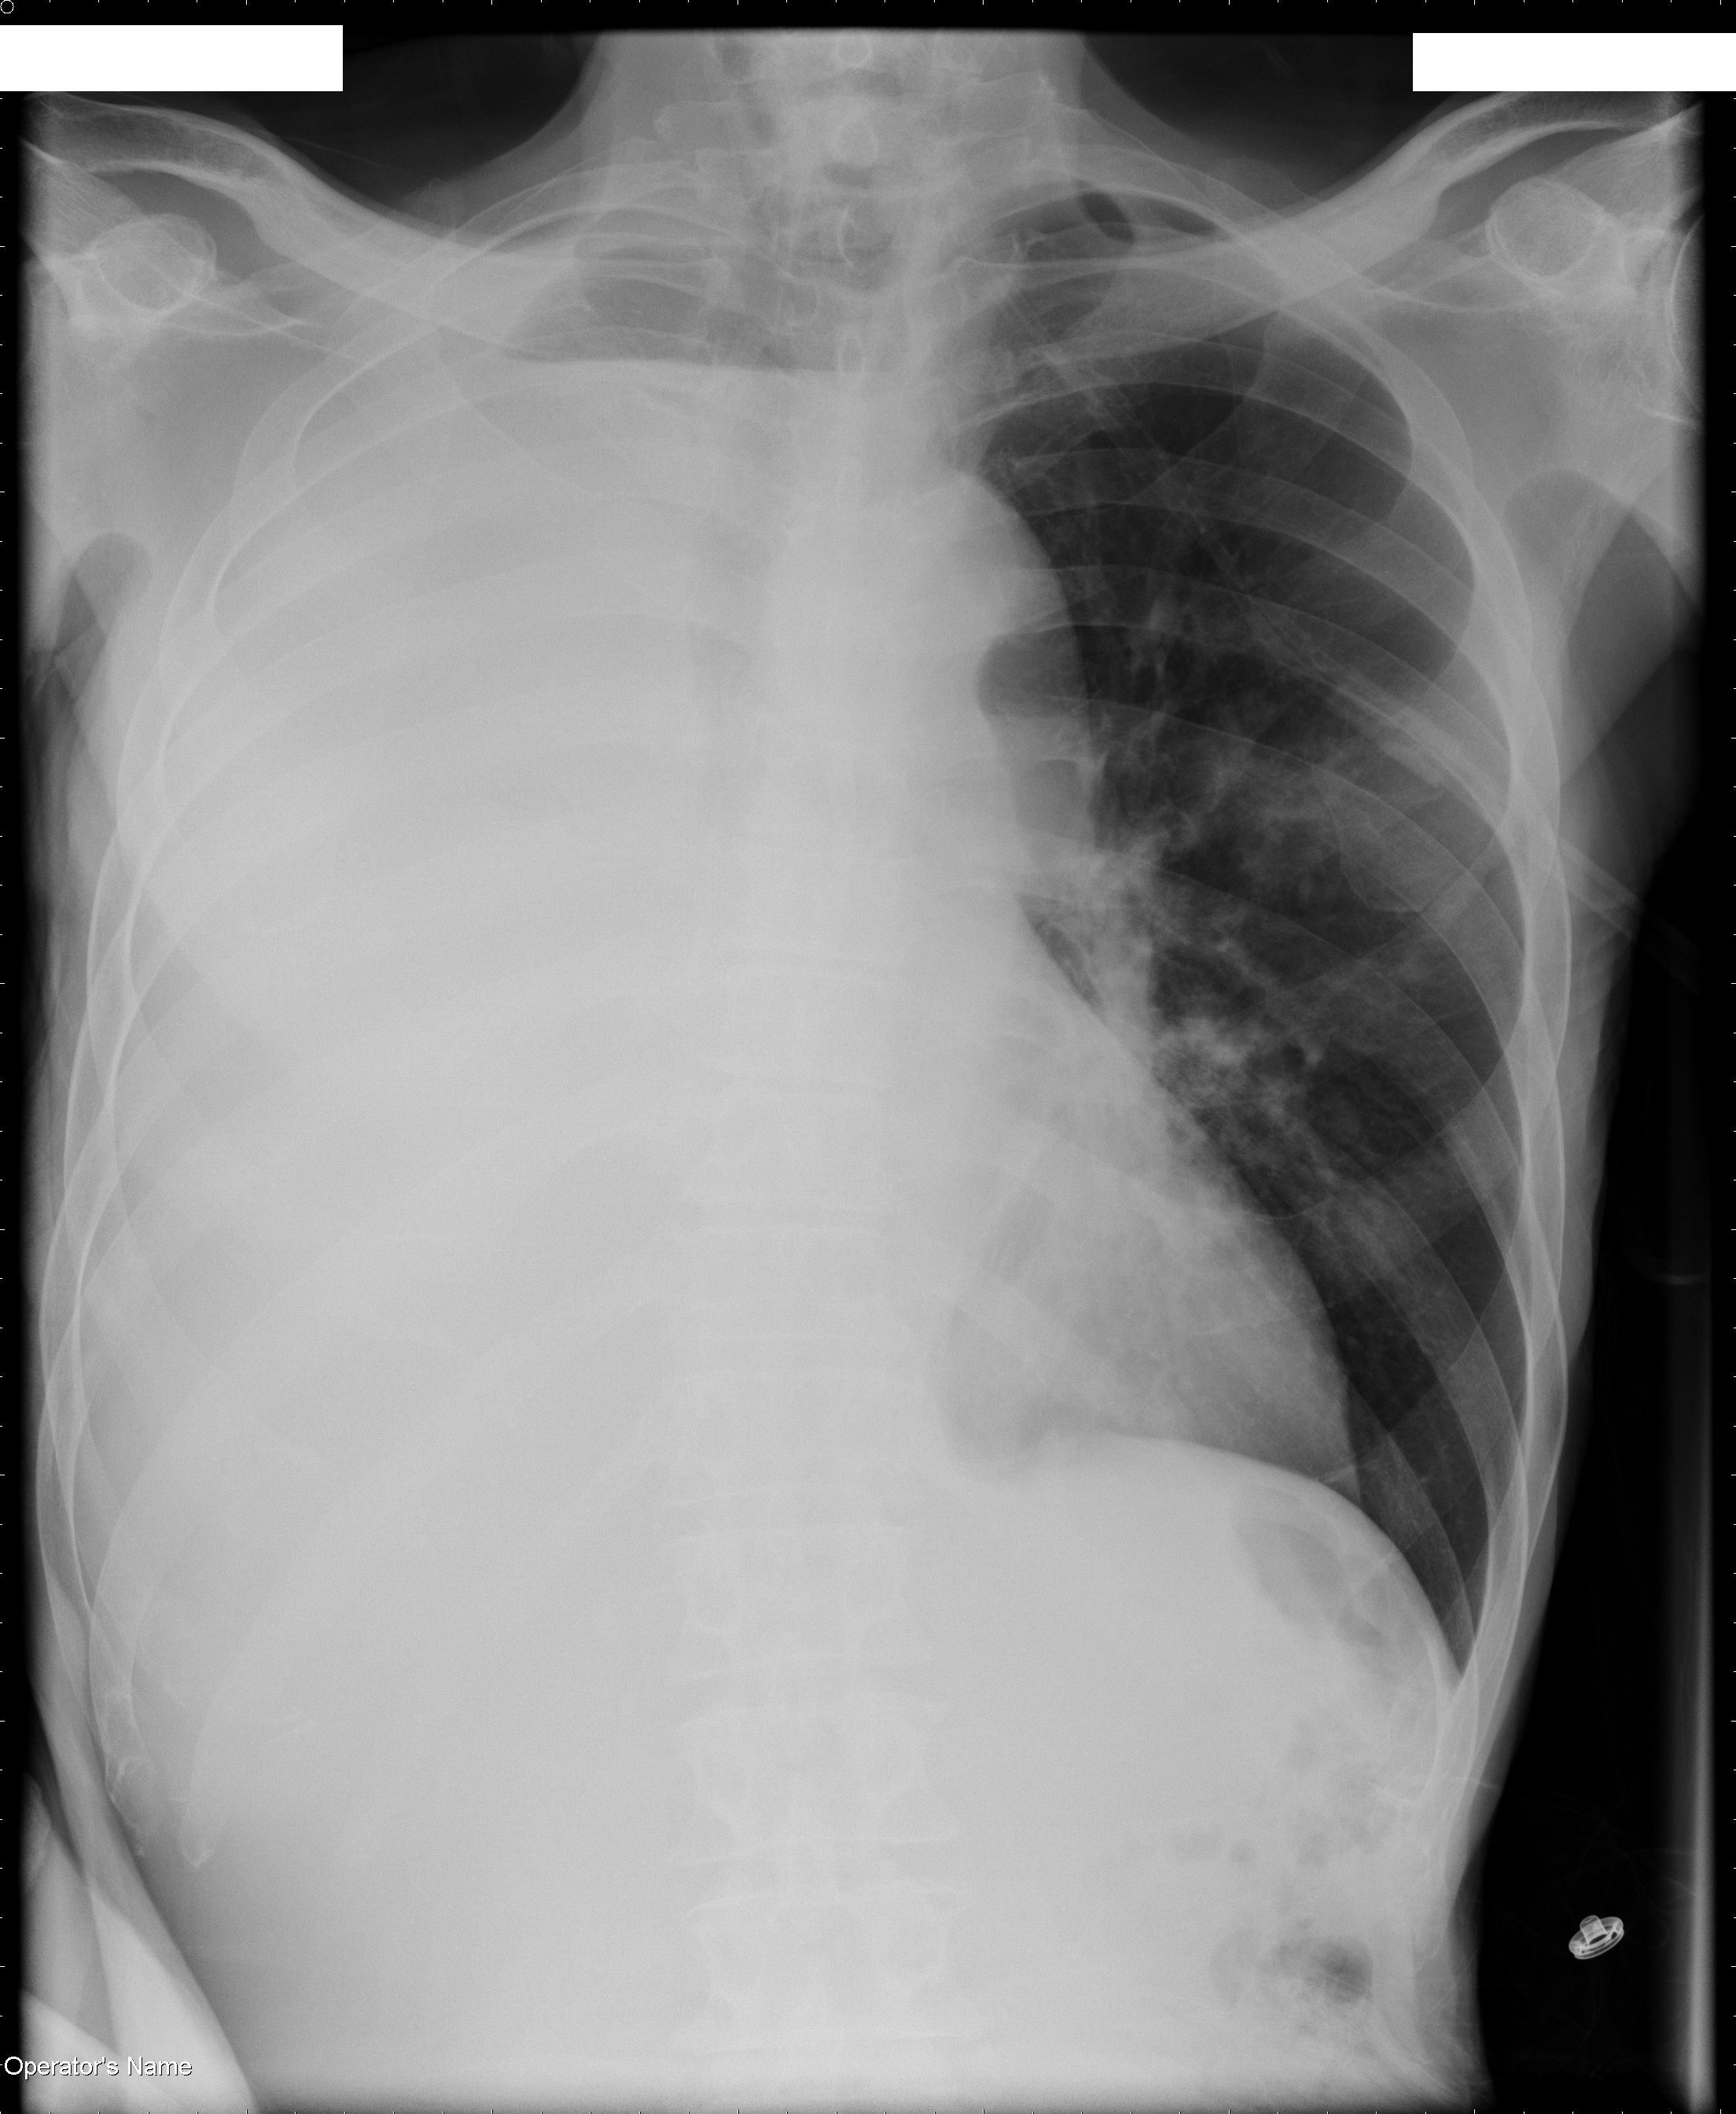

Computed tomography (CT) of the thorax (see Figures 2 and 3) showed a markedly dilated esophagus occupying the right hemithorax filled with a large amount of debris, narrowing of the right mainstem bronchus, total atelectasis of the right lung, a large right pleural effusion and leftward mediastinal shift. The patient's gastrointestinal symptoms, along with the dilated esophagus manifested as the air-fluid level on the chest radiograph, are most consistent with achalasia.

Achalasia alone does not explain the radiographic lung findings. Patients with achalasia are at risk for aspiration and, consequently, pneumonia (2). This can result in bronchial obstruction from mucus or aspirated food particles and subsequent atelectasis. Given the patient's history of productive cough and the radiographic findings, his clinical picture is most consistent with achalasia complicated by aspiration pneumonia, total lung atelectasis and parapneumonic effusion.

Hydropneumothorax can cause an air-fluid level on chest radiograph, but in this case, the air-fluid level does not extend to the lateral chest wall, making this diagnosis less likely. Lung tumors with central cavitation can develop an air-fluid level, and lung cancer can certainly cause both bronchial obstruction and malignant pleural effusion; however, a cavitating tumor with an air-fluid level at the right apex would be an unlikely cause of central airway obstruction and total collapse of the right lung.